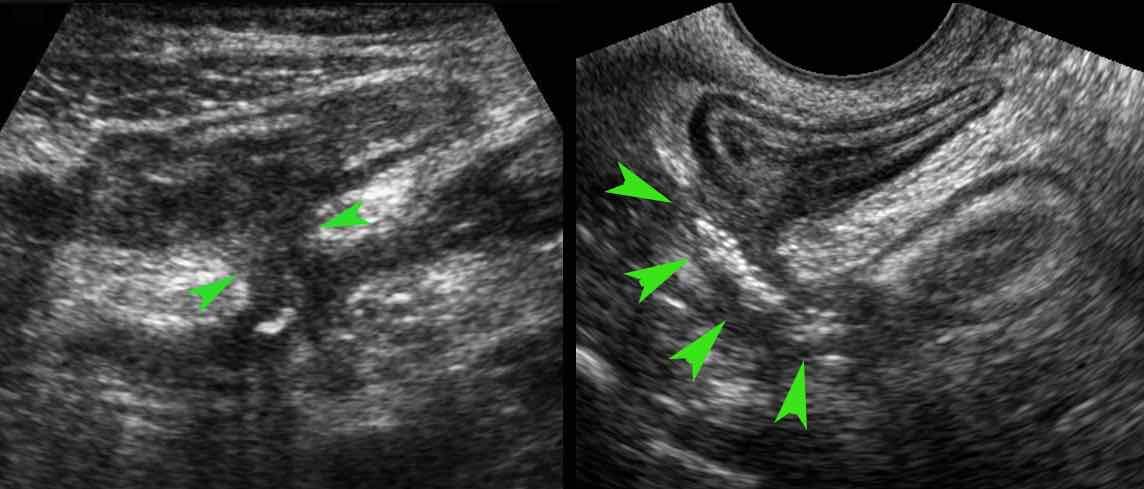

Rò

Cuối cùng, sự hình thành đường xoang có thể tiến triển thành rò.

Đây là hai ví dụ về rò ruột-ruột (đầu mũi tên).